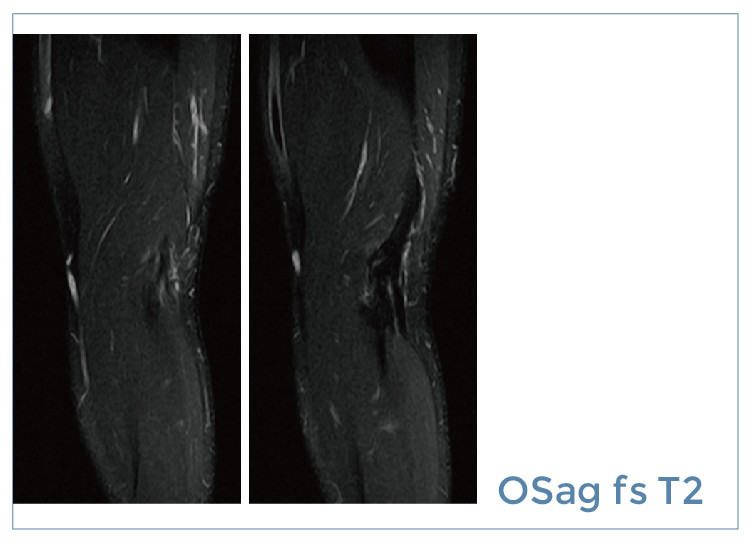

【朗润影像档案】磁共振影像病例分享(编号20190726)